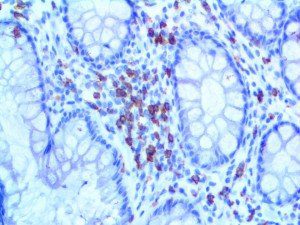

It is the ICU physician who is most likely to witness one of the deadliest manifestations of the abnormal immunological response, the cytokine storm syndrome (CSS). This response is also referred to by some as the cytokine release syndrome (CRS). CSS is characterized by continuous activation and expansion of macrophage and lymphocyte populations, which secrete large amounts of cytokines, causing the cytokine storm. This massive cytokine release is akin to hemophagocytic lymphohistiocytosis (HLH) disease, a syndrome characterized by initial unchecked and persistent activation of cytotoxic T lymphocytes and NK cells.

Clinical and laboratory manifestations of HLH include fever, enlarged liver and/or spleen, neurologic dysfunction, coagulopathy, liver dysfunction, cytopenias (i.e., low levels of erythrocytes, leukocytes, and/or platelets), hypertriglyceridemia, hyperferritinemia, hemophagocytosis, and eventually diminished NK cell activity as the immune system becomes progressively paralyzed. HLH can be familial (primary HLH) or secondary to another disease process (sHLH), such as rheumatic disease, in which it is referred to as macrophage activation syndrome (MAS, characterized by elevated ferritin).